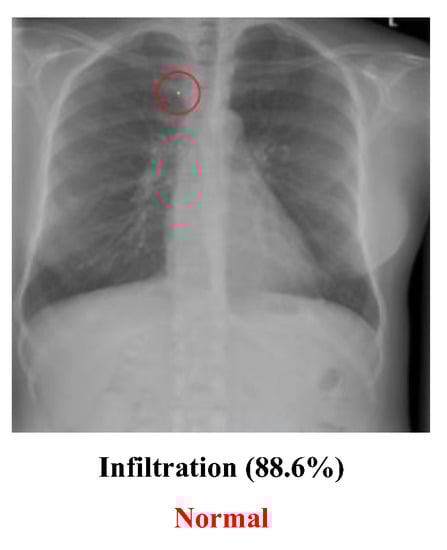

• The medical dataset used for labeling may not be 100% correct. The people who provided the dataset may not have correctly labeled the image, and those who used it may have been unaware of or unable to recognize the mistakes. For example, Figure 11 may not be labeled correctly. Although the image in this dataset is labeled “Infiltration”, which means that the original image had a disease named “Infiltration”, the doctor thought that the image was actually a “Normal” image. He guessed that the lower part of the image might cause the people who labeled the image to think it had been infiltrated, but it may actually be normal muscle cells. The problem of incorrect labeling questions the use of an open-source dataset;

Figure 11. Wrongly labeled image.